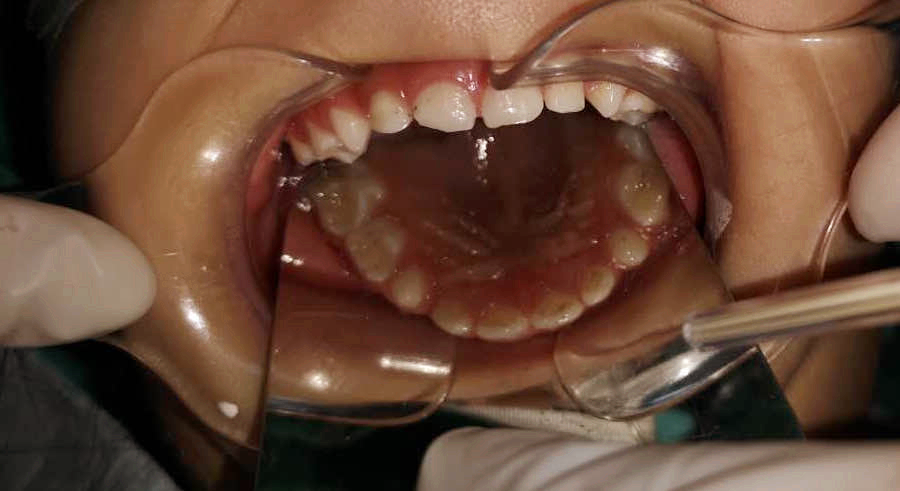

調(diào)節(jié)后